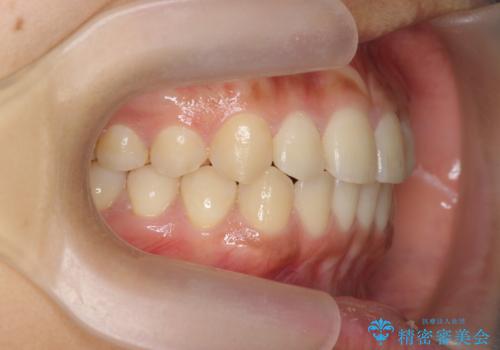

- 前歯のガタつき、上下たがい違いになっている歯並び(クロスバイト)の改善を求めて来院されました。

インビザラインによる矯正治療を行いますが、クロスバイトの改善をワイヤー部分矯正で事前に行うことにより治療期間の短縮する治療計画を立案します。

上下すれ違った噛み合わせはマウスピースでは改善に時間がかかり、またねじれが残ってしまうことも多々見られます。

マウスピース矯正を行う前に、これらの症状の改善の得意なワイヤー部分矯正を行うことで治療期間を短縮し、確実にすれ違いを改善することができます。